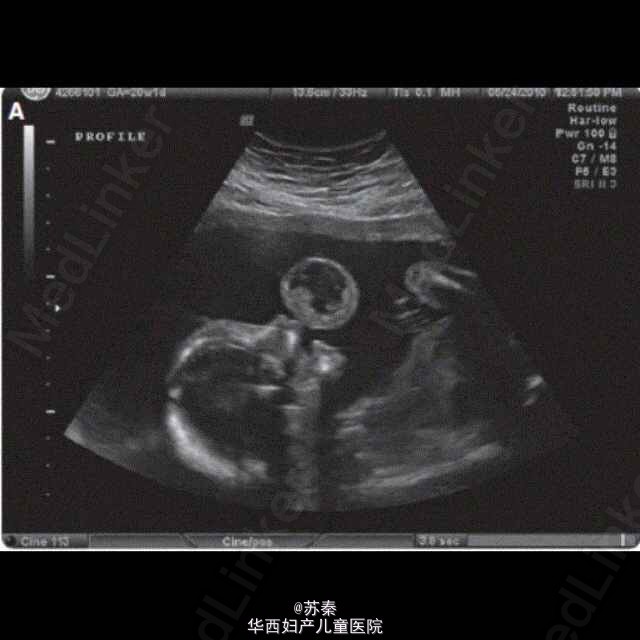

37岁女性,G4P1031,孕20周做超声提示在胎儿口腔内有一带蒂囊性含固体内容物的肿块。多普勒显示该肿瘤的动静脉图像。MRI提示在胎儿脸部靠近正中偏左处发现外生型复杂肿块,未发现颅内转移。 各种影像学资料综合,提示为胎儿的口腔部畸胎瘤。 选择做胎儿镜经胎儿嘴唇和上颚将肿块去除。 产妇生产后,检查胎儿口腔,无明显裂痕,伤口或残余肿块。